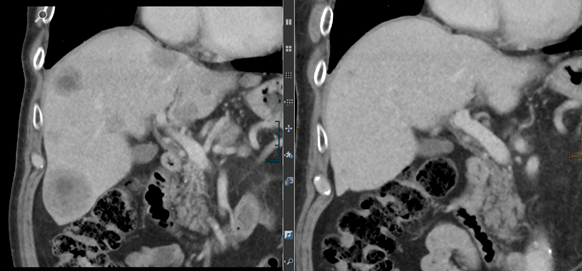

Die Röntgenaufnahme von Bernd Kirchhausens Leber: Links mit Metastasen (schwarze Punkte) aus 2015, rechts die aktuelle befundfreie Aufnahme.

Das Prinzip der Immuntherapie: Inzwischen gibt es Antikörper, die genau dieses PD-L1-Signal der Tumorzelle ausschalten und damit wieder das Immunsystem gegen den Tumor aktiv werden lassen. Die Erfolge sind wahrlich bahnbrechend. Seit Oktober 2015 ist Bernd Kirchhausen Immuntherapie-Patient. Alle zwei Wochen geht er für kurze Zeit in die Onkologische Praxis von Dr. Peter Liebisch, der eng mit den Bethanien-Fachärzten zusammenarbeitet, und bekommt eine Infusion mit dem Medikament Nivolumab. Das Ergebnis zeigt das kleine Bild im Artikel. Die Leber von Bernd Kirchhausen ist frei von Metastasen. Die Mediziner sind weit davon entfernt zu sagen, dass Immuntherapie Patienten heilen kann. "Nicht jeder Tumor spricht auf diese Therapie an. Aber bei manchen Patienten fördert sie die Remission der Tumore", erklärt Peter Liebisch. Sprich: Der Tumor wird zurückgedrängt.